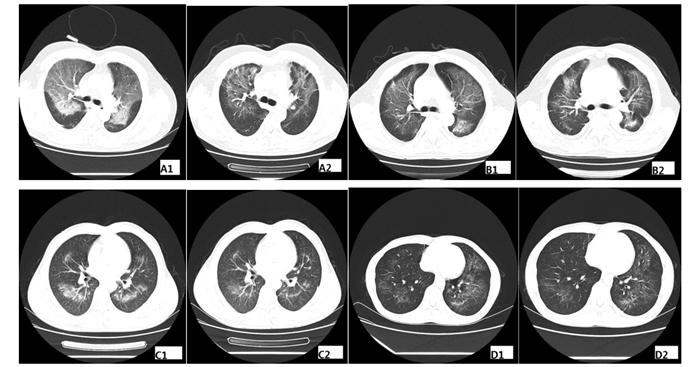

2.3.4 胸部CT

患者入院时胸部CT检查均显示,两肺弥漫性斑片影及磨玻璃样密度影。28 d后复查CT仍然存在斑片状渗出(图 3)。

A1、A2为A患者治疗前后比较;B1、B2为B患者治疗前后比较;C1、C2为C患者治疗前后比较;D1、D2为D患者治疗前后比较 图 3 4例患者胸部CT表现 Figure 3 CT appearance of lung of patients

吸入性金属镍中毒的损伤机制主要是对肺泡Ⅱ型上皮细胞的直接损伤。目前无吸入性金属镍中毒对其他系统造成损伤的报道。其临床表现主要为呼吸系统损伤的症状。本组病例的临床特点如下:早期症状不典型,呼吸道症状和肺部影像学改变分别出现于接触后56 h、66 h、68 h、120 h,此前表现为乏力、发热而无呼吸道症状,均误诊为感冒;患者均出现白细胞总数增高,病情越重,白细胞总数越高;肝肾功能未见明显损伤。患者胸部CT主要表现为两肺弥漫性斑片影及磨玻璃样改变,肺部病灶大小与病情严重程度相关。患者肺功能检查显示为限制性通气功能障碍和弥散功能障碍。